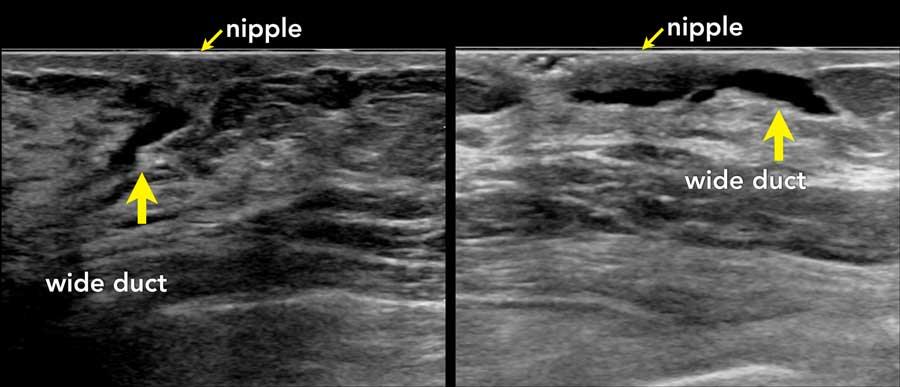

Vùng núm vú có thể khó khảo sát.

Trong hầu hết các trường hợp, chỉ thấy hình ảnh dày da nhẹ và phía sau núm vú có một số ống tuyến giãn.

Hình ảnh này của một bệnh nhân đến khám với triệu chứng núm vú bị tụt vào trong.

Có một khối u bờ không đều phía sau núm vú với hình ảnh xâm lấn vào núm vú (mũi tên).

Đây là một khối u khác phía sau núm vú (n).

Các khối u này có thể rất khó phát hiện.

Ở mọi phụ nữ có triệu chứng núm vú tụt vào trong, vùng này cần được khảo sát cẩn thận.